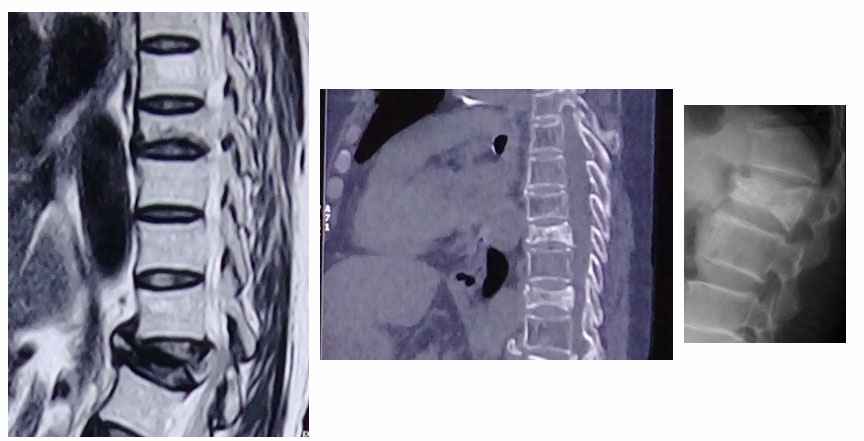

MRI and CT scan gives better visualization to decide the level and extent of fracture than X-ray.